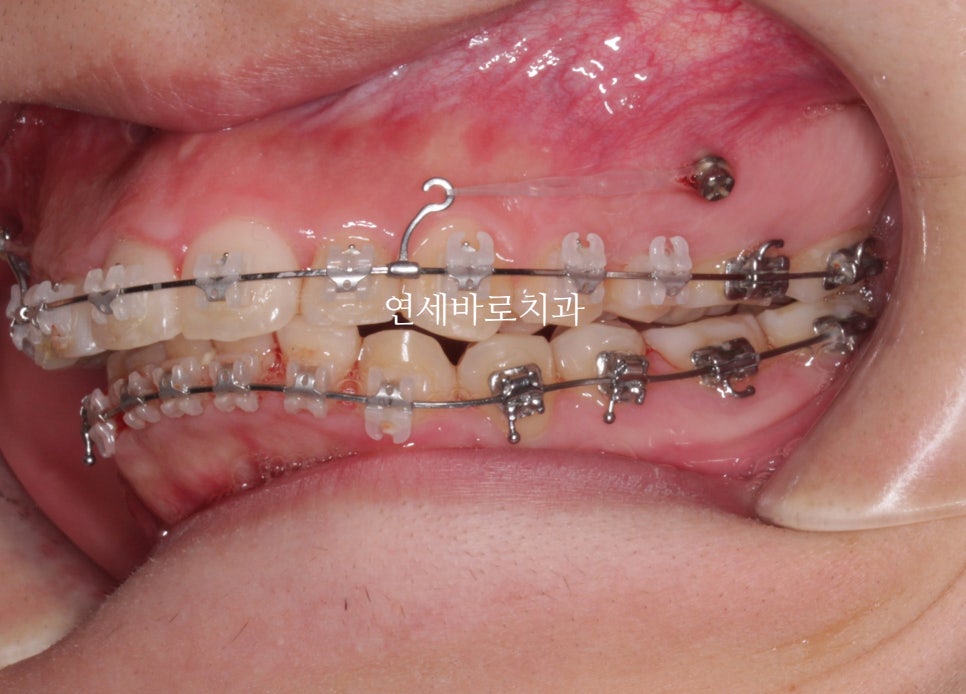

어느정도 준비를 하는 배열의 시간이 지나가고 #미니스크류 를 식립했습니다.

환자분의 골격상태 등을 고려하여 진단했고, 미니스크류를 많이 심진 않았습니다.

위쪽은 2개 심고 치료를 마무리 했습니다.

아래쪽은 중심선을 맞추기 위해 편측으로 1개만 식립.

시간이 오래 지났지만 계속 당기기만 합니다.

당기면 들어갑니다.

뒤에 공간만 있으면 뒤로 갑니다.

공간은 CT등을 통해 지속적인 확인을 하면서 진행합니다.